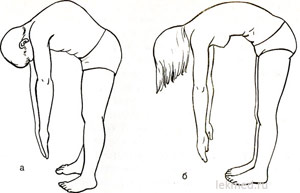

Hozzájárulás a kezelésére kyphosis felnőtteknél a gyakorlatsort. megerősítését célzó körüli izmok a gerinc:

- Feküdjön a gyomorban. Kapunk mögött torna botot, és megnyomja azt a lapátok behajlítva, a könyök, a csukló. Elkezdjük görbe a törzs.

- Legyen négykézláb. A mellkas legyen megereszkedik a földre, fejét, karját behajlítva, a könyök. Ebben a helyzetben, feltérképezni legalább 40 lépésben.

- Feküdjön a gyomorban. Taken félre vagy feladja, hogy a súlyzó. Elkezdjük kiegyenesíteni a törzs.

A hatás lehet pozitív, fontos, hogy végre a gyakorlatokat helyesen és rendszeresen.